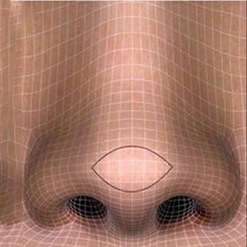

Yestar艺星从宫廷袜子的设计中获得了灵感,发现鼻尖与袜尖一样,只有具备一定的圆润度和翘度,才符合人体的自然曲线。由此,Yestar艺星明确了鼻尖的俏、和、挺、润度,才是真正决定鼻子好看与否的核心标注,并且研发出了BSK宫廷隆鼻术。

Yestar宫廷隆鼻塑造鼻尖不仅效果,而且由于软骨具有良好的柔韧性,大大减少了对鼻尖的磨损,技术中采用自体筋膜组织为鼻尖软骨做保护垫,在塑造的鼻尖表现点的同时,对鼻尖起到双重保护的作用,更避免鼻尖成形不自然的情况,塑造出的鼻尖线条流畅、唯美自然。

Yestar艺星医生根据"双曲线"设计比例,对自软骨从正面到两侧面边缘进行精细到微米的高难度微弧度雕琢,并确保与鼻部皮肤的衔接将自然流畅。术后鼻部将呈现出两条自然的美人弧线,鼻部立体感更强,不仅肉眼看不出破绽,用手摸完全无法察觉有什么不同,鼻子宛若天生,从视觉上和触觉上都达到美学新高度。

用鼻中隔软骨与耳软骨综合塑造鼻尖,恰到好处地弥补了传统单纯采用耳软骨或自体软骨塑造的缺陷,将两种材料有机结合使用,优缺点互补,同时通过鼻部左右软骨的顶部与鼻尖上区转折点、鼻小柱-小叶角构成的四个点位进行鼻尖微调,将鼻尖部皮肤支撑到较为的角度,这样会让鼻尖更稳固、更,且看起来饱满圆润,生动娇俏不生硬,塑造出的鼻尖玲珑有致!

鼻根至鼻小柱底部呈流畅S曲线;鼻翼至鼻孔内侧呈柔美S曲线。

鼻尖上表现为水平走形的高光区,斜面上看是有柔和的鼻尖转折。

仰面等边三角形支决定鼻部立体感。

鼻根呈倒三角;鼻尖鼻头呈悬胆形态,鼻孔与鼻尖鼻小柱形成女性的美学海鸥线。